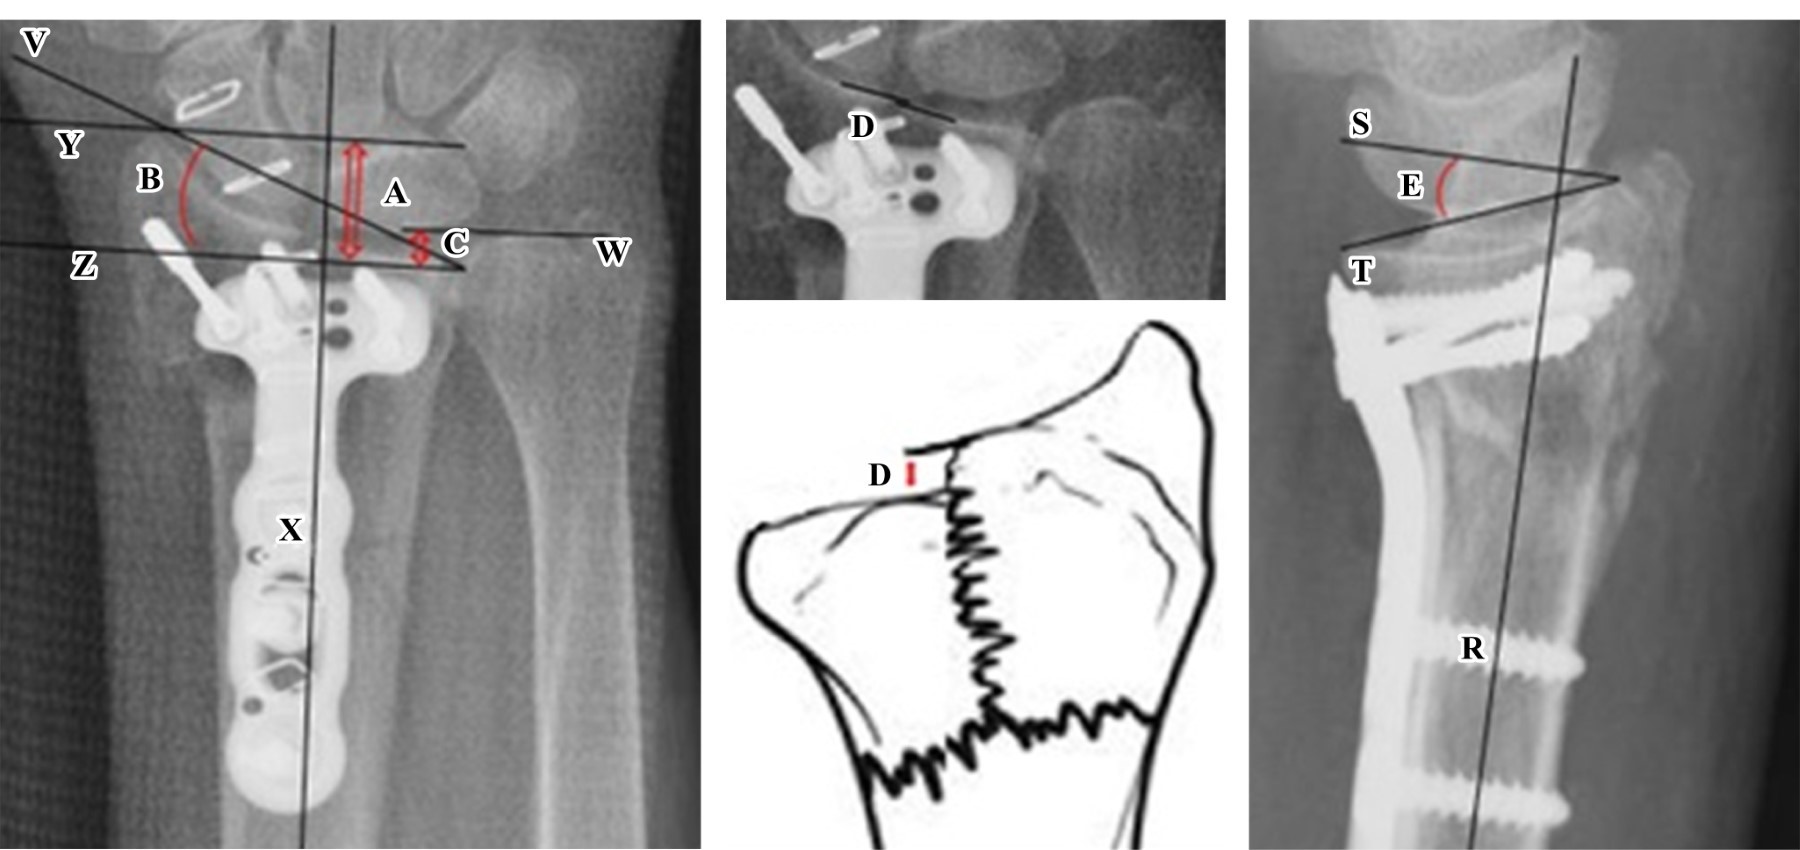

Figure 1